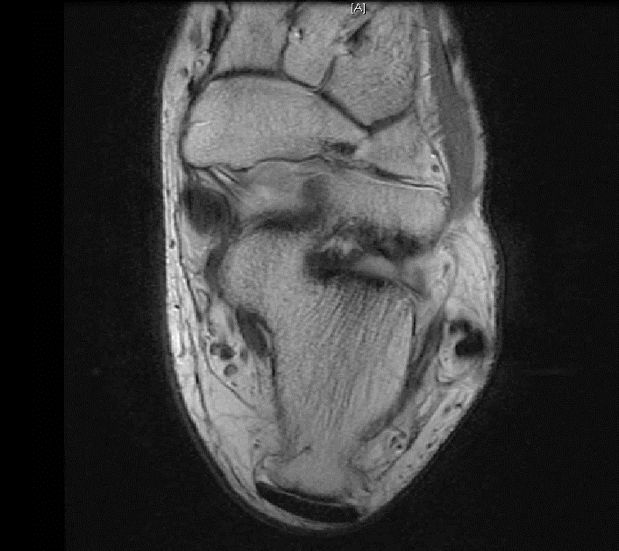

从这张片子我们可以看到正常的韧带结构,包括距腓前韧带,跟绯韧带,它是质地比较均一,T2相高信号,连续性良好,并且有良好的张力,从冠状位也可以看到跟绯韧带,在腓骨肌腱的深方,也是T2相跟T1相的低信号,有良好的连续性,张力也不错。